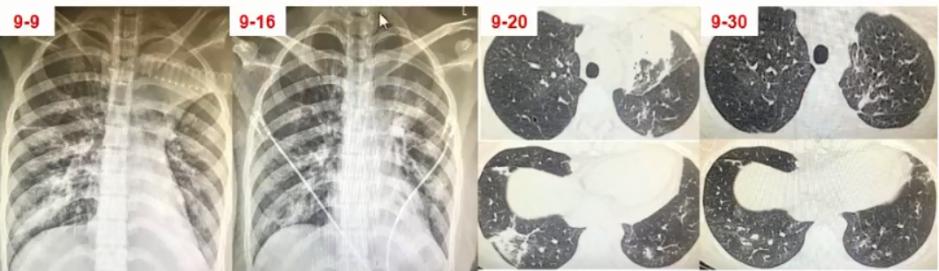

图6 患者在院外胸部影像学变化。左上肺小块实变,逐渐累积至右下肺,而且左上肺实变扩大和膨胀不全。

图7 患者入院当日病情小结

图8 患者入院当日胸部CT。左上肺大面积实变,右上肺斑片影,出现胸腔积液